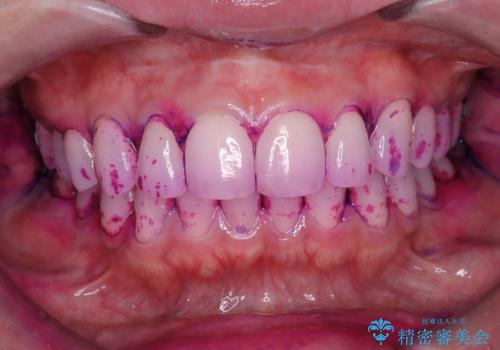

着色は少ない口腔内でしたが、染め出しをしてエアフローを行いました。

汚れが少なく見える口腔内でも染め出しをすると歯茎の近くなどに汚れが溜まっているのがわかります。